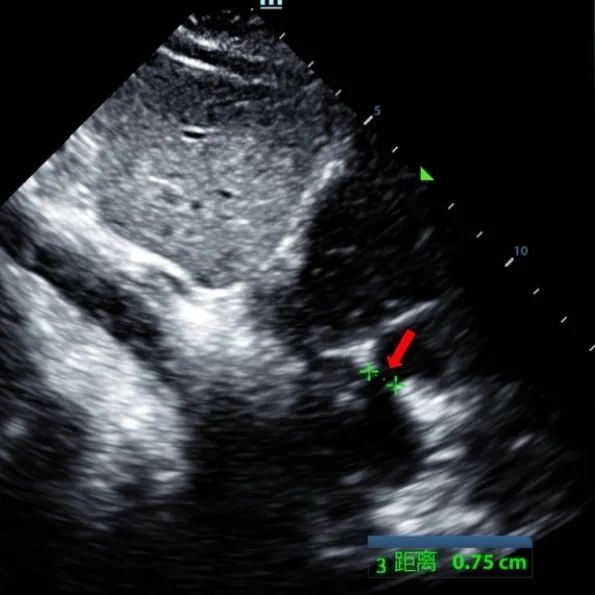

Secundum asd (7.5-7.9mm) ile 9 yaşındaki bir erkek, memosorb BDASD-I 12mm occluder ve 12f dağıtım sistemi kullanılarak tedavi edildi. Komplikasyonlar veya komorbiditeler ön prosedür olarak belirtilmedi.

Serial echocardiographic follow-ups showed stable device position and favorable cardiac remodeling. Gradual degradation confirmed the occluder's long-term safety and efficacy.